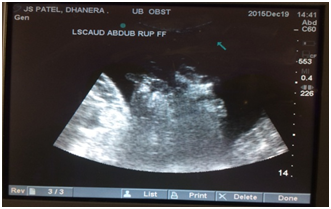

The eye mucus membrane was pale to pale-pink in four and congested in five calves. Similar observations were noted by Parrah et al.,2 and Tamilmahan et al.,6 in urinary retention cases. The mean heart rate, respiration rate and temperature were found within normal physiological limit at the time of presentation and on 12th day after surgery (Table 2). However Kushwaha et al.,3 and Tamilmahan et al.,6 observed tachycardia and tachypnoea with normal rectal temperature in buffalo calves with urolithiasis. Ultrasound is a non invasive diagnostic tool used for examination of urinary bladder, as small bladder cannot be detected by abdominal palpation or radiography.7 Trans-abdominal B-mode ultrasonograhic examinations with 3.5-5.0MHz transducer visualized the urinary bladder in all calves. In present study free fluid in abdomen and empty urinary bladder with floating abdominal organs (Figure 4), mainly intestine were observed in 6 calves with cystorrhexis, while in one calf subserosal urinary bladder rupture was observed, indicated by distended urinary bladder along with free fluid in abdomen. Similar findings were recorded in cases of urinary bladder rupture by Parrah et al.2 In two calves distended intact urinary bladder was imaged with dilated neck (Figure 5) having multiple hyper echoic foci without acoustic shadow which might be urinary sediments. Parrah et al.,2 have reported hyperechoic foci in distended urinary bladder of calves suffering with obstructive urolithiasis.

Figure 5 Real time B-mode ultrasonogram of caudal ventral abdomen showing distended urinary bladder having echogenic deposits..